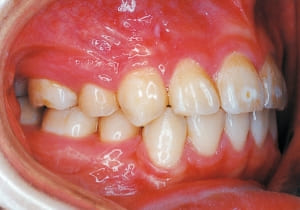

2 After Phase 2 Treatment 6-6-’94

The first phase of treatment involved extracting the left and right maxillary deciduous canines. The space created was used to forcibly retract the four anterior teeth, thereby aiming to improve lip closure function (6–9, 11). Morphological changes suggest that lip function differed before and after treatment (6, 9). Subsequently, the first premolars erupted, but extraction is planned to secure space for canine eruption (10). A Class II molar relationship remains, but the significant overjet has improved (11).

In the maxilla, insufficient space for canine eruption was inevitable, necessitating extraction as part of the treatment plan. The maxillary first premolars on both sides were extracted during routine observation to create space for canine eruption (14). Eventually, the canines erupted and settled into relatively favorable positions (15,19,20). In the mandibular dentition, crowding was also present, leading to extraction of the mandibular first premolars on both sides. Treatment with full bracket was then initiated (17).